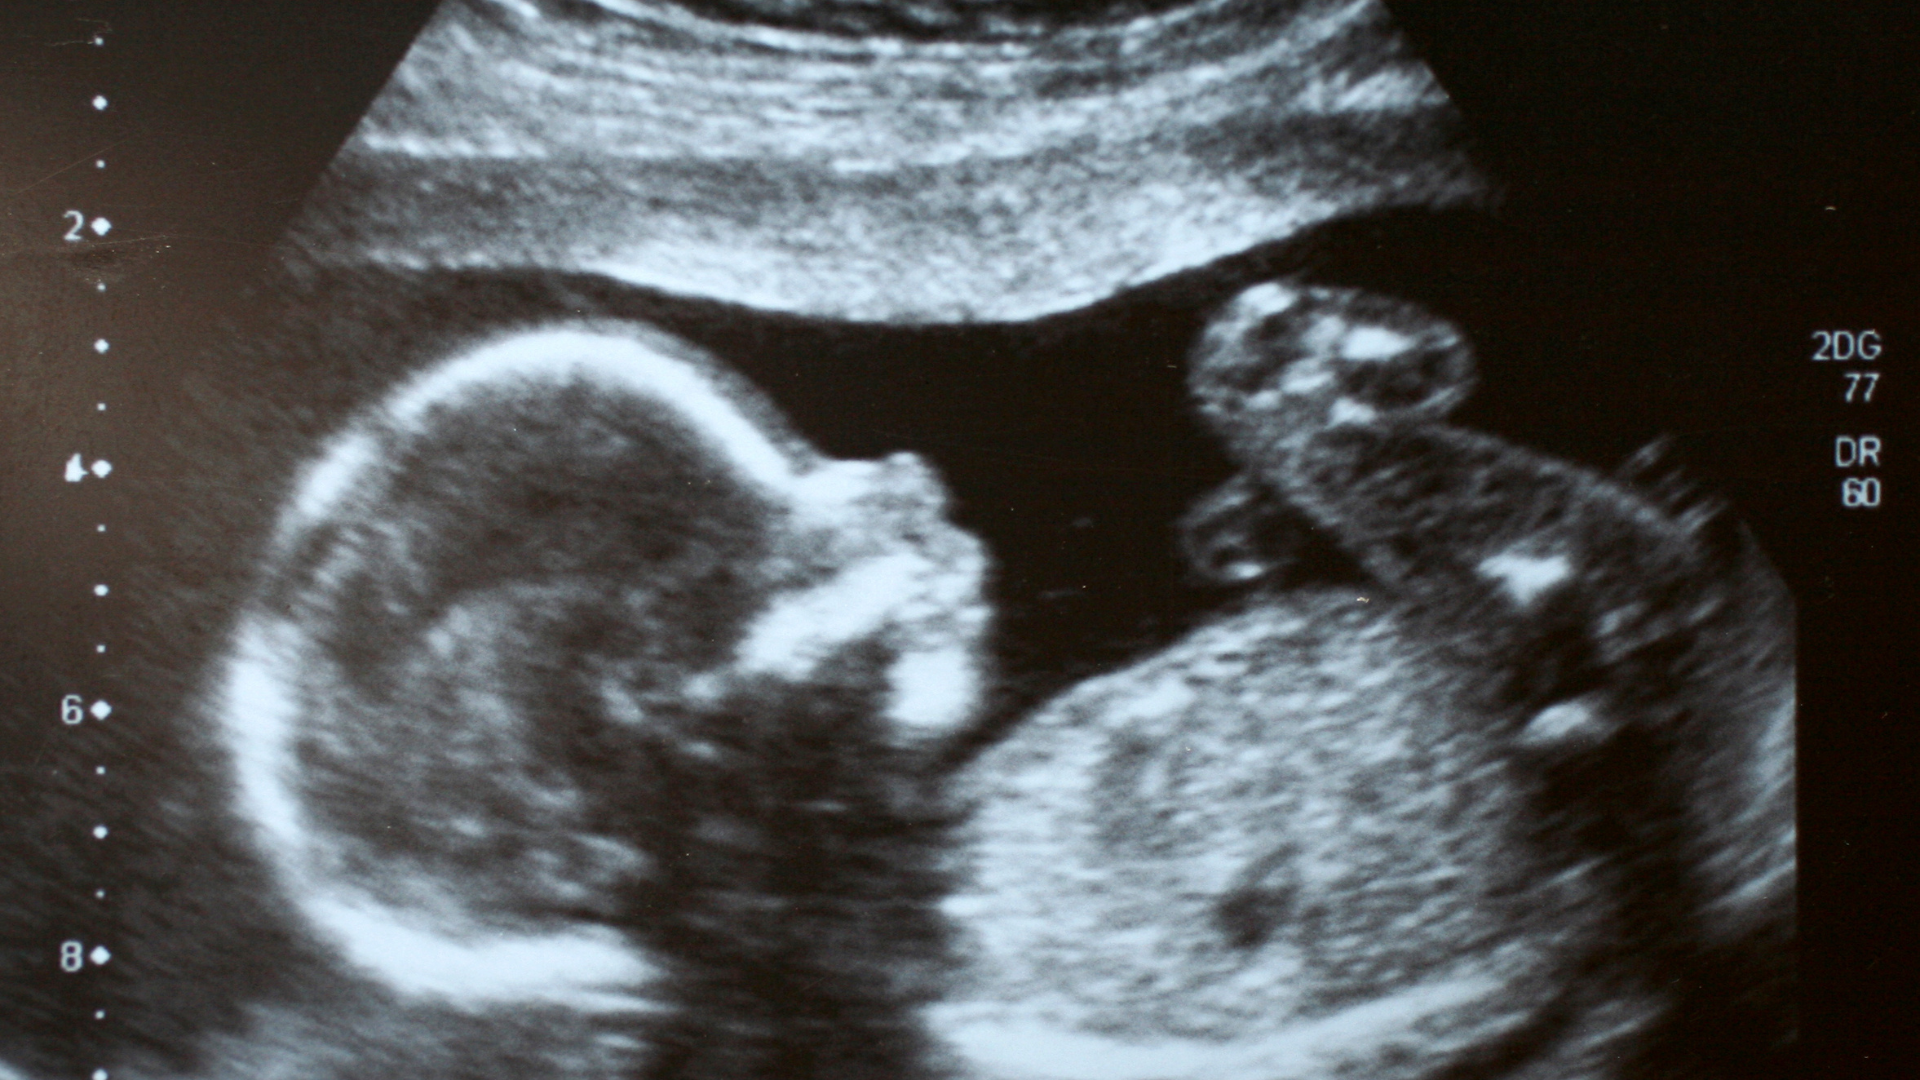

Có nhiều phương pháp để đánh giá lượng nước ối, trong đó siêu âm là phương pháp chính xác và đáng tin cậy nhất. Tuy nhiên, các dấu hiệu lâm sàng và cảm nhận chủ quan của mẹ bầu cũng có giá trị tham khảo, đặc biệt khi chưa đến lịch siêu âm.

Siêu âm đo chỉ số ối (AFI) - tiêu chuẩn vàng

Đây là phương pháp phổ biến và chính xác nhất để đánh giá lượng nước ối. AFI (Amniotic Fluid Index) được tính bằng cách chia tử cung thành bốn phần và đo chiều sâu của túi ối lớn nhất trong mỗi phần.

- Bình thường: AFI 8 - 18 cm.

- Thiểu ối: AFI < 5cm (hoặc túi ối sâu nhất < 2cm).

- Đa ối: AFI > 25cm (hoặc túi ối sâu nhất > 8cm).

Trong thực tế, bác sĩ không chỉ dựa vào một lần đo mà sẽ đánh giá kết hợp với sự phát triển của thai, tình trạng nhau thai và sức khỏe mẹ để đưa ra kết luận chính xác hơn.